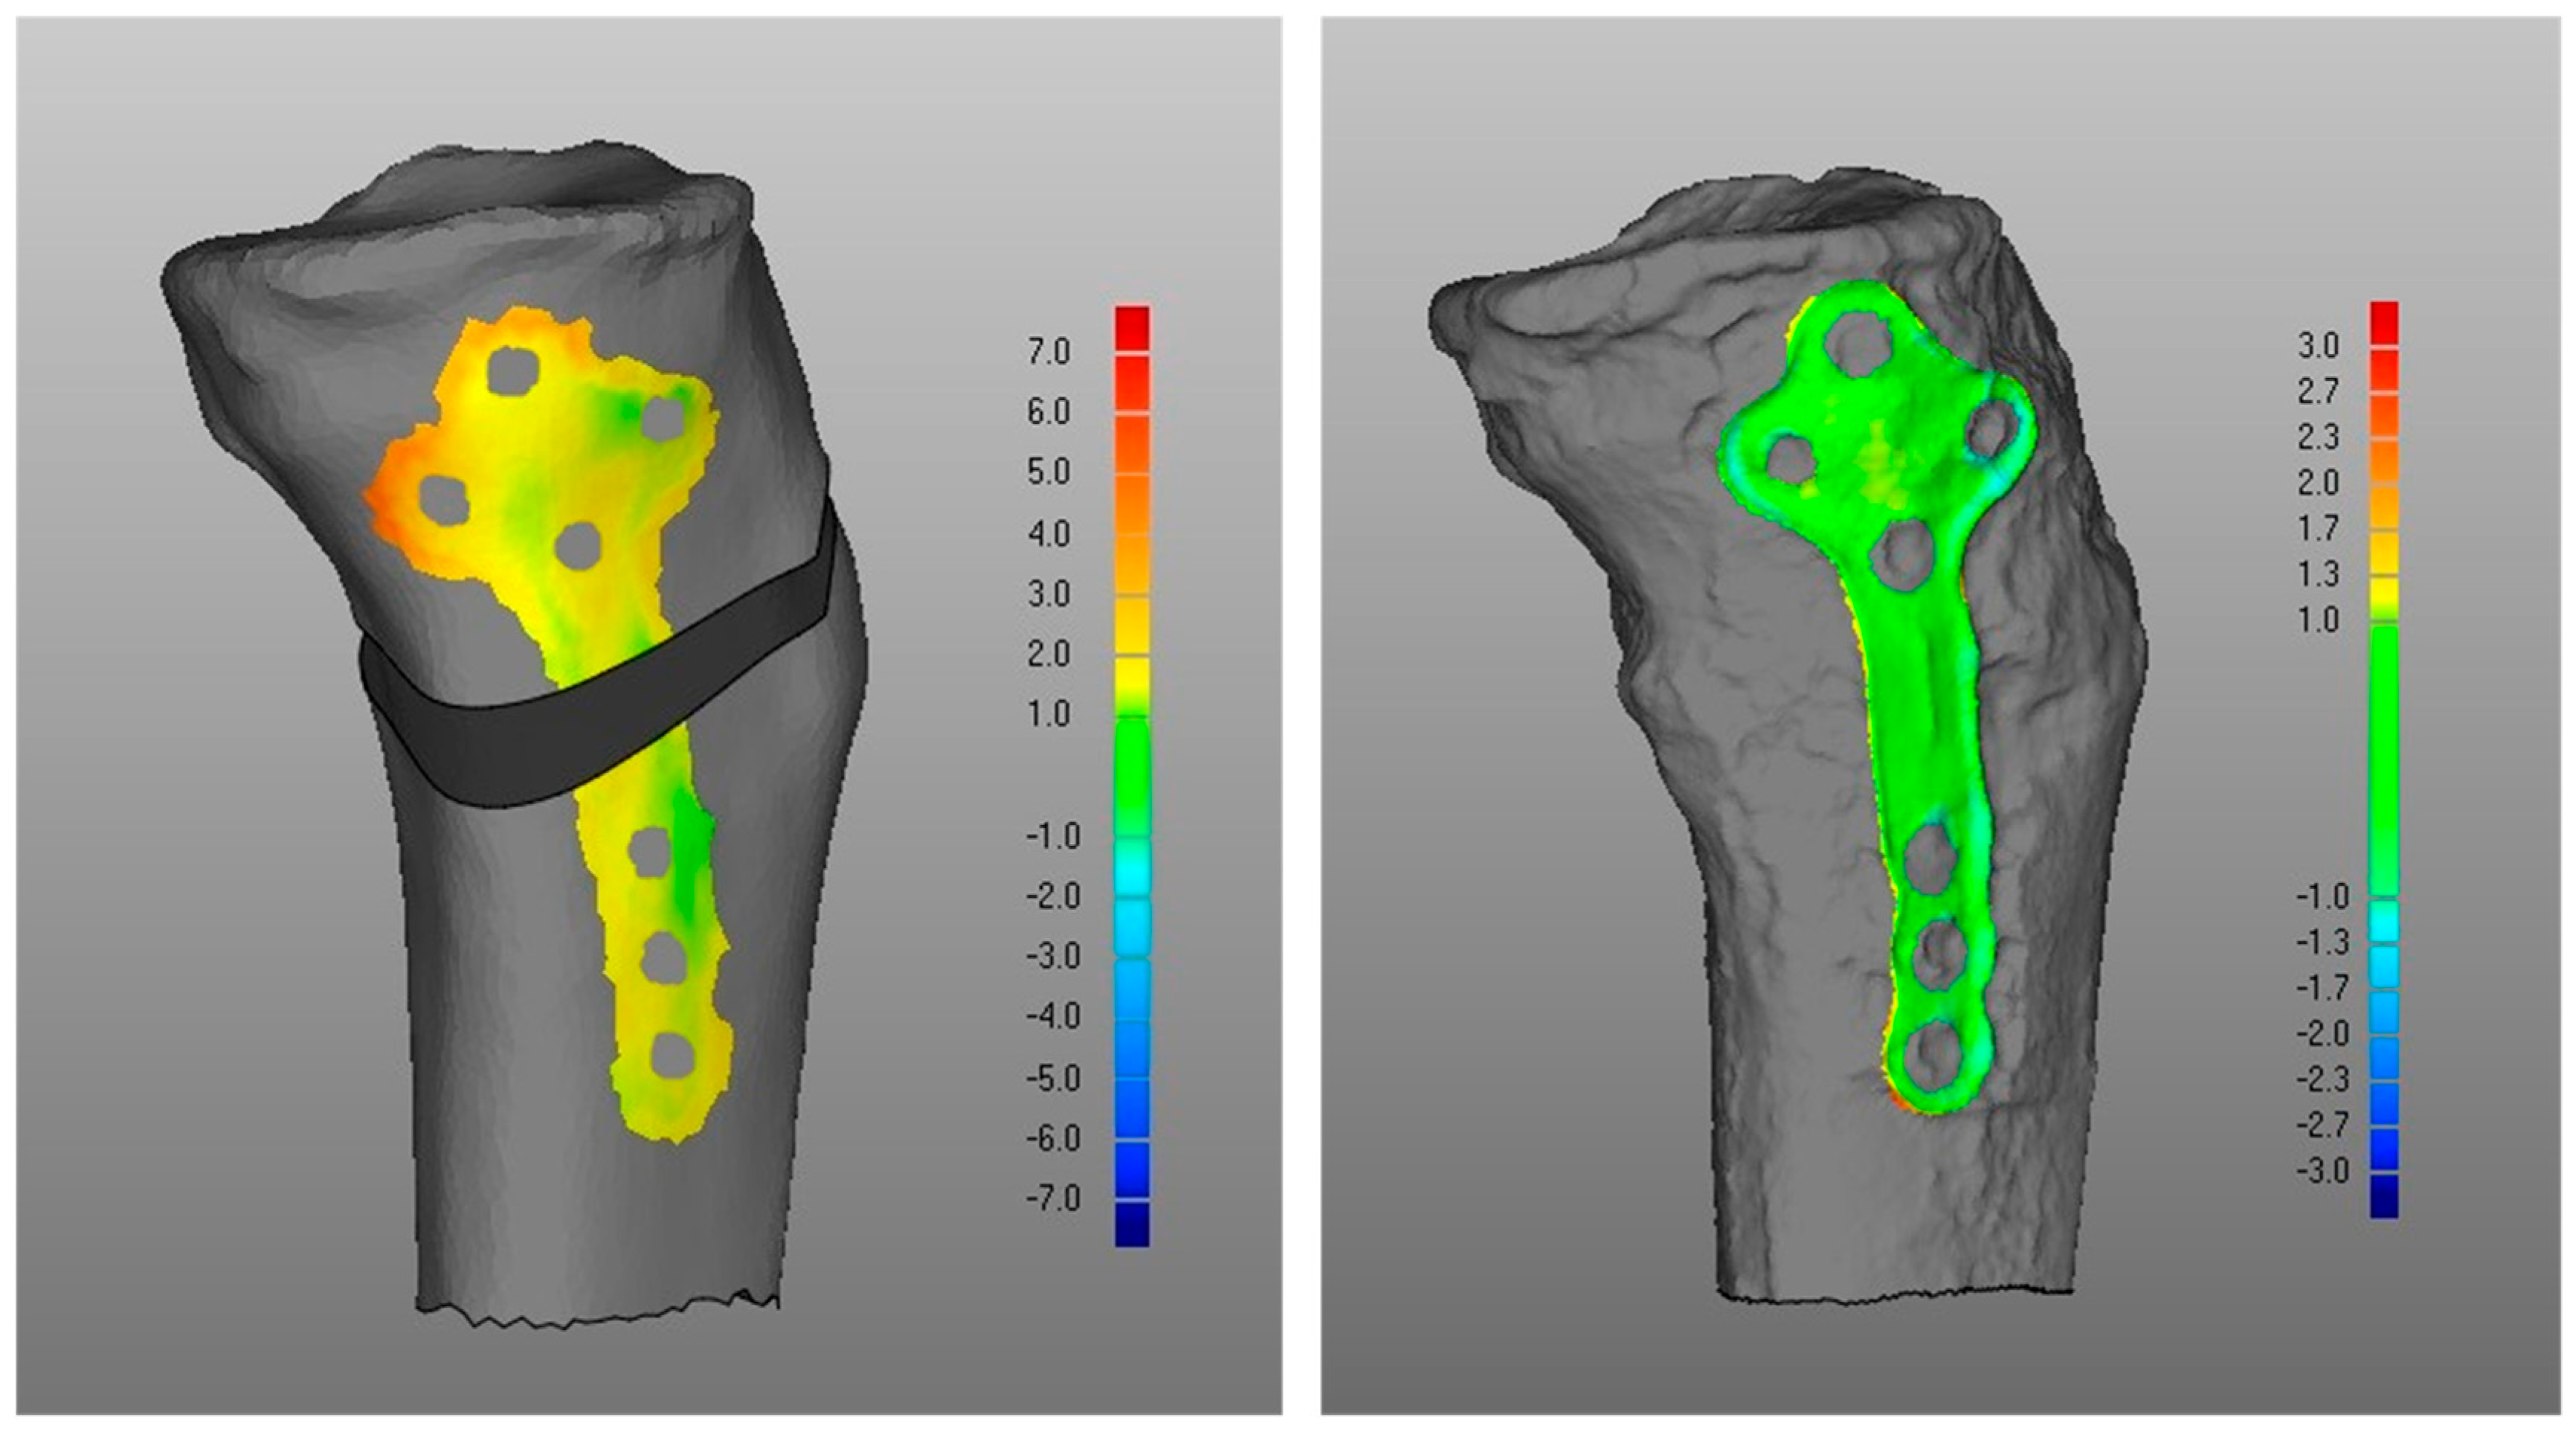

- Overall, a good replication of PLA tibia morphology was achieved in POST (Figure 3 and Figure 4), with average values for of 1.4 mm and of −0.9 mm, associated with very small DMA standard deviation (DSD average value 1.6 mm) over the entire patient cohort (Table 1). Most points were in the safe zone (Table 2), although discrepancies were observed, mainly due to the difficulty of excluding the bone allograft (used to fill the osteotomy cut which is the standard practice of the operating surgeon) during image segmentation, thus altering the morphology of the area around the osteotomy in POST with reference to the corresponding one in PLA.Table 1. DMA outputs (units for all variables mm). = Positive mean Distance, = Negative mean Distance, DSD = DMA standard deviation.Table 1. DMA outputs (units for all variables mm). = Positive mean Distance, = Negative mean Distance, DSD = DMA standard deviation.

- Regarding the matching of the plate surface contour to the tibia, the comparison between PLA, i.e., iii-a (Figure 6 left), and POST, i.e., iii-b (Figure 6 right), the low DMA values (Figure 3 and Table 1) reveal a very good replication of the planned contour matching of the plate to the tibia in the POST condition. In iii-a comparison, there was no negative value, i.e., penetration, of the test surface relative to the reference (Table 2).